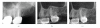

Cone Beam Computed Tomography (CBCT) is a diagnostic imaging modality that provides high-quality, accurate three-dimensional (3D) representations of the osseous elements of the maxillofacial skeleton. CBCT systems are available that provide small field of view images at low dose with sufficient spatial resolution for applications in endodontic diagnosis, treatment guidance, and posttreatment evaluation. This article provides a literature review and pictorial demonstration of CBCT as an imaging adjunct for endodontics.